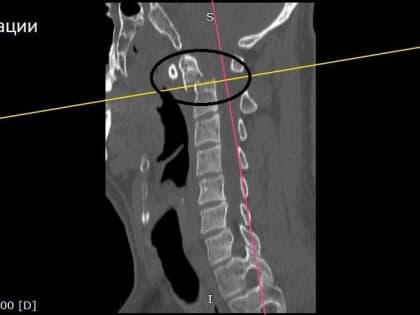

Операция по стабилизации перелома шейного позвонка в Воронеже

Местный житель получил травму в результате падения и успешно перенес хирургическое вмешательство.